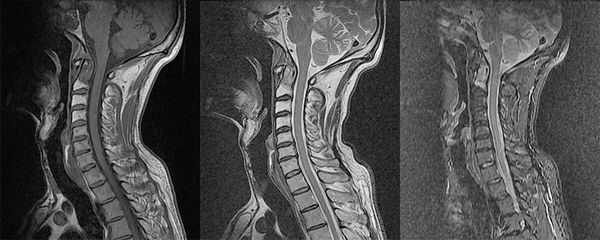

МРТ мягких тканей шеи не включает осмотр шейного отдела позвоночника, так как для него нужен другой режим работы томографа. При необходимости, если есть подозрения на патологию позвоночника или спинного мозга, в комплексное томографическое обследование добавляют и этот вид сканирования. Тогда можно определить грыжи шейного отдела позвоночника, признаки остеохондроза, сдавление спинного мозга и его корешков.